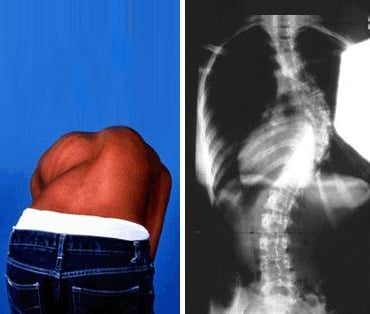

بروز في الأضلاع أو الظهر

عند الانحناء إلى الأمام (مثل ربط الحذاء)، قد يبدو أحد جانبي القفص الصدري أو أسفل الظهر أعلى أو أكثر بروزًا من الآخر — وهي علامة شائعة على دوران العمود الفقري المرتبط بالجنف.

تساعد هذه النتائج الموضوعية على تحديد ما إذا كان الجنف موجودًا، وطبيعة انحناء العمود الفقري، وما إذا كانت هناك حاجة إلى رعاية إضافية — مثل المتابعة الدورية، أو إعادة التأهيل، أو استخدام الدعّامات — وفقًا للحالة.